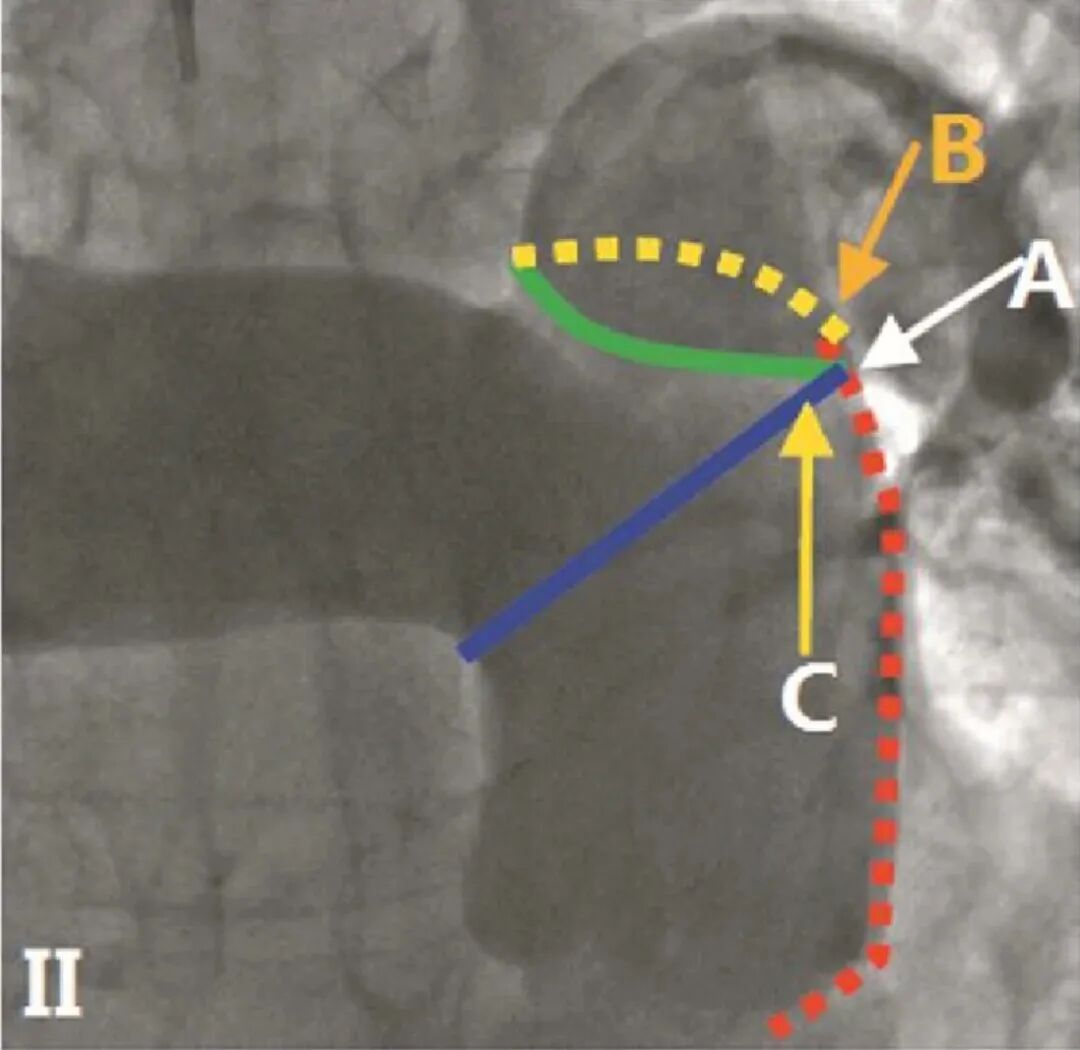

PADN术消融黄金三靶点

通过对比术前超声、CT报告及术中造影,选定消融靶点和50mm射频消融导管(按测量直径1.1-1.2倍选择导管)。交换导丝导管,建立消融通道。

通道建立后,进入消融导管,调整合适位置后进行消融。

首次消融位置

二次消融位置